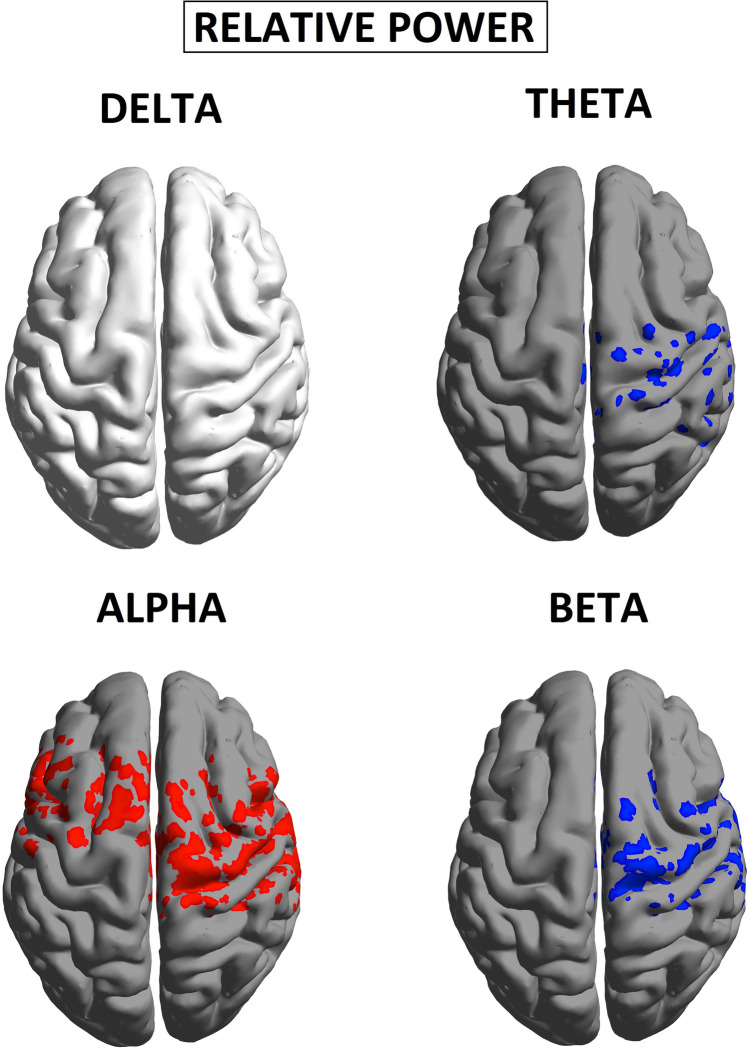

Group spectral power in patients compared with healthy controls

An overview of the results obtained is provided in Table 1, as specifically shown in Fig 2 resting state EEG showed significant increases in spectral power for CUD patients compared with controls across all four frequency bands, albeit this effect was most distributed in the alpha band (Fig 2). To improve specificity, we tested for differences in relative (%) power, often used to normalize spectra under a constant value of broadband (1-40 Hz) power, and reflecting the degree of spectral slowing (i.e., greater relative power in lower frequencies) or spectral acceleration (i.e., greater relative power in higher frequencies). As shown in Fig. 2, patients demonstrated regions of anatomically selective excess of slow-waves amplitude (alpha), in line with previous research (Kalivas & O’Brien, ref. 2008). Specifically, relative alpha power was significantly more elevated in the cortex of patients relative compared with controls (Fig 3), with a statistical threshold of p < 0.05 at a t-values of t >1.67.

CUD was associated with relative alpha power increases within frontocentral regions, with a maximum in the sensorimotor cortex (t = 2.11, p < 0.05). On the other hand, relative theta and beta power were reduced within the temporal lobe (t = −1.99, p < 0.05; t = −1.87, p < 0.05 respectively). No significant differences were found in the delta band.